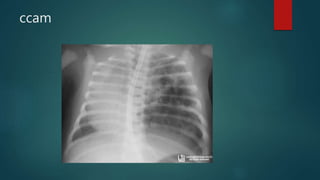

ccam